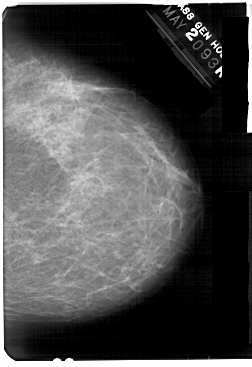

A_1369_1.RIGHT_MLO

RIGHT_MLO LINES 5491 PIXELS_PER_LINE 3796 BITS_PER_PIXEL 12 RESOLUTION 43.5 NON_OVERLAY